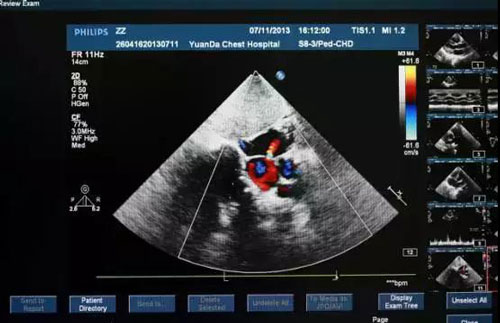

心臟檢查方式二:心臟彩超

“此項(xiàng)目能檢查房間有多大,墻結(jié)不結(jié)實(shí),漏不漏水。”

醫(yī)生通過(guò)在患者體表移動(dòng)探頭,能清楚地看到心臟結(jié)構(gòu),相當(dāng)于醫(yī)生的“透視眼”,如心壁厚薄、心腔大小、心臟瓣膜啟閉等情況,還能直觀顯示心肌的運(yùn)動(dòng)狀況及血流動(dòng)力情況,提示心肌缺血的部位等,且對(duì)人體沒(méi)有任何損傷。